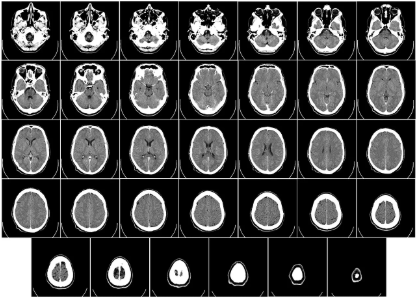

현대 의료 진단의 핵심 장비인 컴퓨터 단층 촬영기, CT는 지난 수십 년간 비약적인 발전을 거듭하며 현대 의학 진단의 필수 장비로 자리 잡았습니다. 과거에는 상상조차 할 수 없었던 빠르고 선명하며 정밀한 영상을 이제는 당연하게 얻고 있죠. 이러한 CT 발전의 숨은 주역 중 하나는 바로 X선 정보를 포착하는 검출기(Detector)입니다. 그리고 이 검출기 기술의 눈부신 진화 여정에는 반도체 기술이 핵심 동력으로 작용해 왔습니다.

CT 검출기는 단순한 X선 센서에서 시작하여 반도체 기술과 만나면서 완전히 새로운 차원으로 발전했습니다. 과연 CT 검출기는 반도체 기술과 함께 어디까지 진화해 왔을까요? 그 흥미로운 진화의 발자취를 따라가며 반도체 기술이 CT 검출기를 어떻게 변화시켰는지 알아보겠습니다.